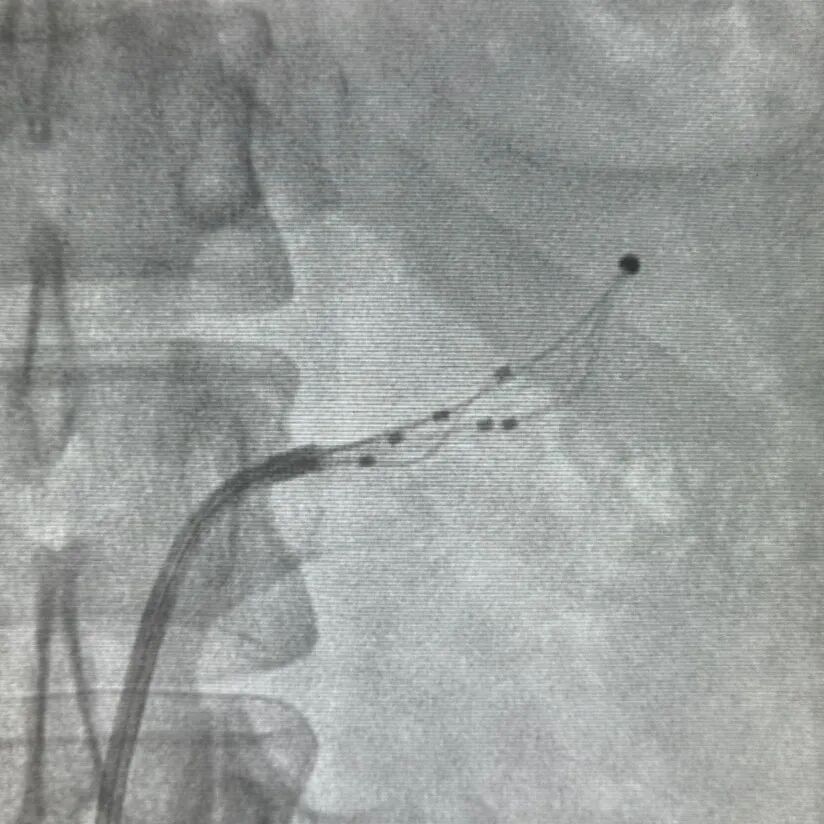

术前DSA造影

术中消融

术后造影

患者全麻后经右侧股动脉途径将网篮六电极射频消融导管送入右肾主干远端,由远及近消融4次,共计消融20个位点,消融峰值能量9W,然后将消融导管导管送入左肾主干,行5次消融,共计消融18个位点,造影复查肾动脉未见夹层、痉挛等并发症。